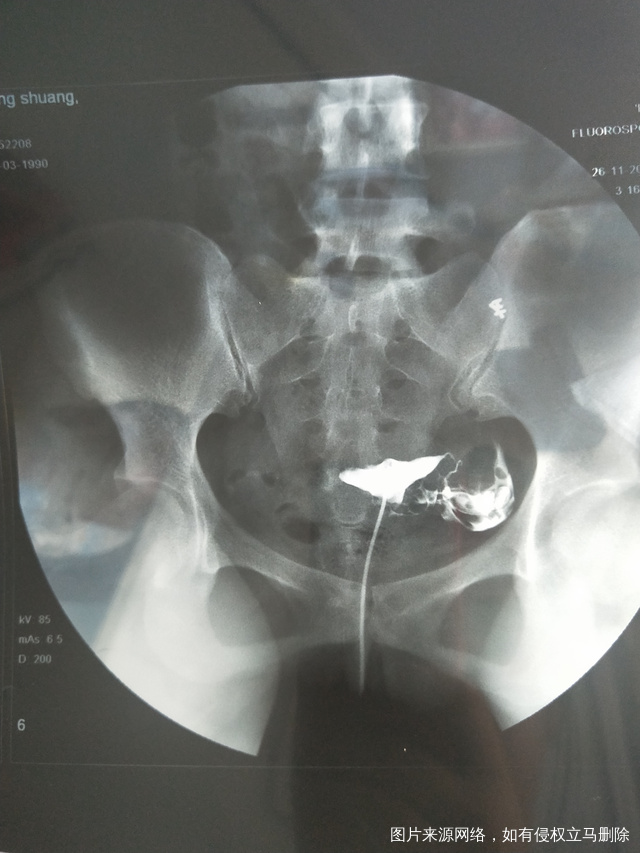

帮忙看一下造影片子,谢谢